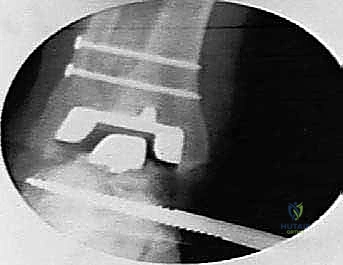

1. مكون ظنبوبي (Tibial Component): قطعة معدنية تُثبت في عظمة الساق (القصبة). الميزة العبقرية لنظام Agility هي أنه يتطلب دمج المفصل الظنبوبي الشظوي السفلي (Tibiofibular syndesmosis). هذا يعني أن الجراح يقوم بدمج عظمة القصبة مع عظمة الشظية لإنشاء قاعدة عريضة وقوية جداً تدعم المفصل الصناعي وتمنع ارتخاءه بمرور الوقت.

4. تحضير العظام ودمج القصبة والشظية

هذه هي الخطوة الأكثر حيوية في نظام Agility. يتم إزالة الغضروف التالف والزوائد العظمية. ثم يتم تحضير السطح السفلي لعظمة القصبة (Tibia) والسطح العلوي لعظمة الكاحل (Talus) باستخدام أدوات قطع دقيقة لضمان ملاءمة مثالية للمفصل الصناعي. بالتوازي، يتم تجهيز المسافة بين القصبة والشظية ووضع طعوم عظمية (Bone Grafts) لضمان التحام العظمتين معاً، مما يشكل قاعدة صلبة للمكون العلوي.